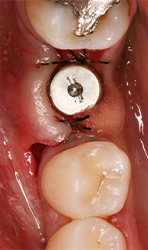

The Magnetic Max (Figs. 1-2) is useful for conservative root extraction.

Fig. 2

Maximum preservation of the alveolar housing and related gingival structures may be achieved following assisted atraumatic tooth extraction by an electrical mallet (Fig. 3).